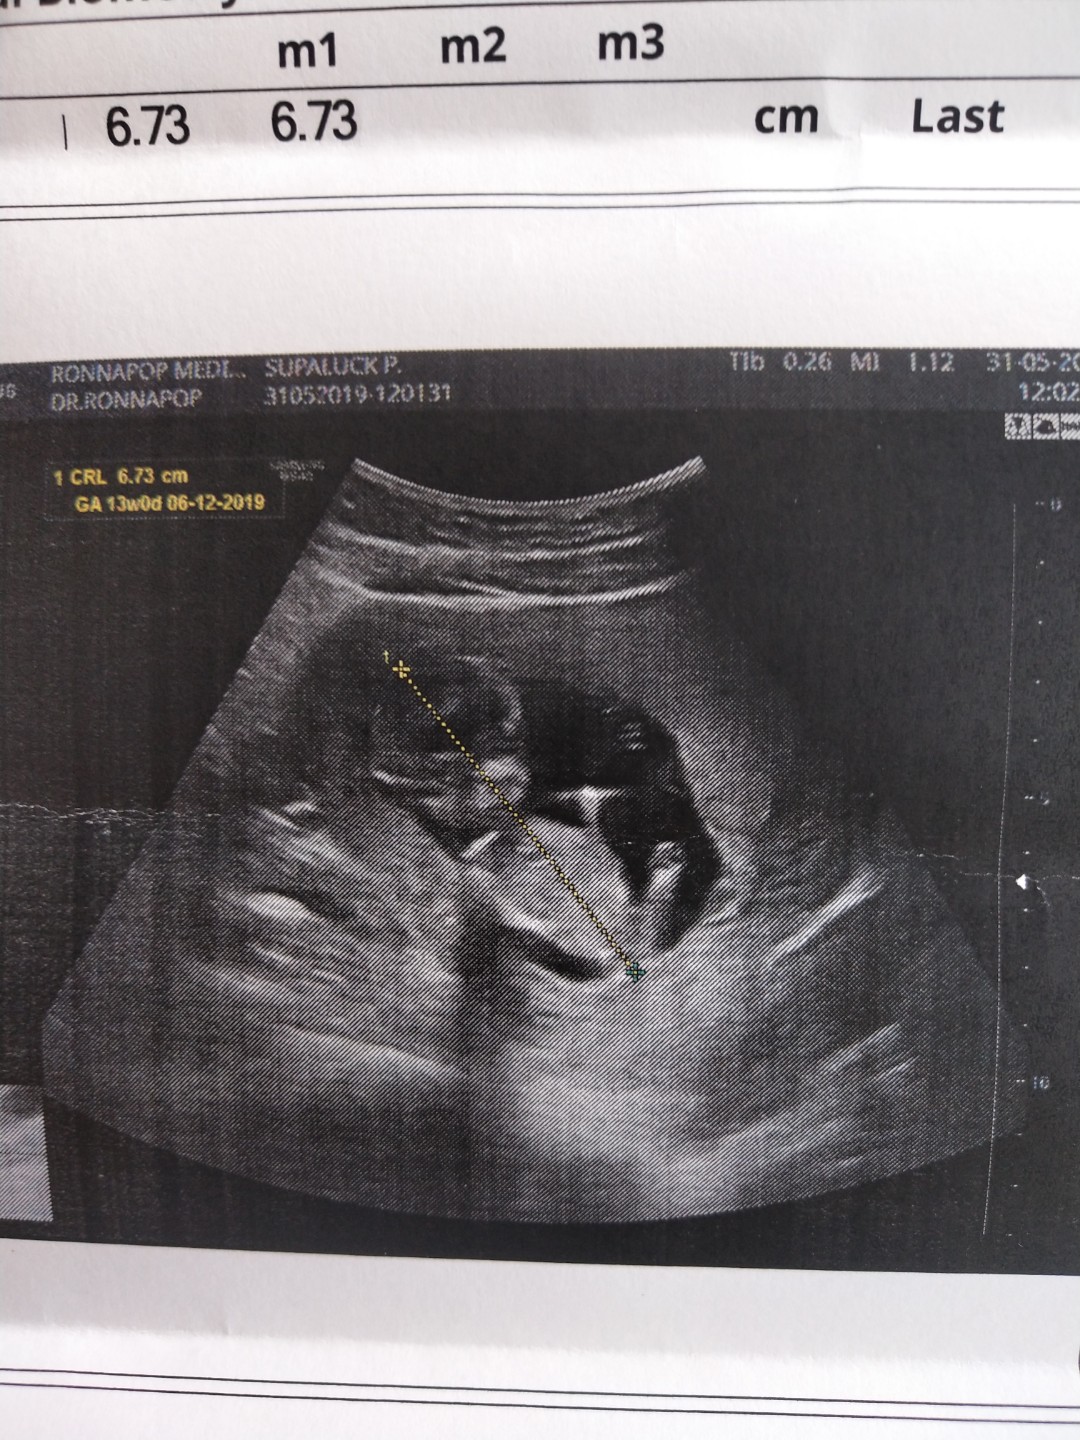

แม่ๆคนไหนมีภาพอัลตร้าซาวด์ประมาณ13วีคบ้างคะ ของเรา13วีค ภาพแบบนี้ค่ะ ดูไม่ออกเลย?

ในภาพ 13w5dคะ แต่น้องตัวโต